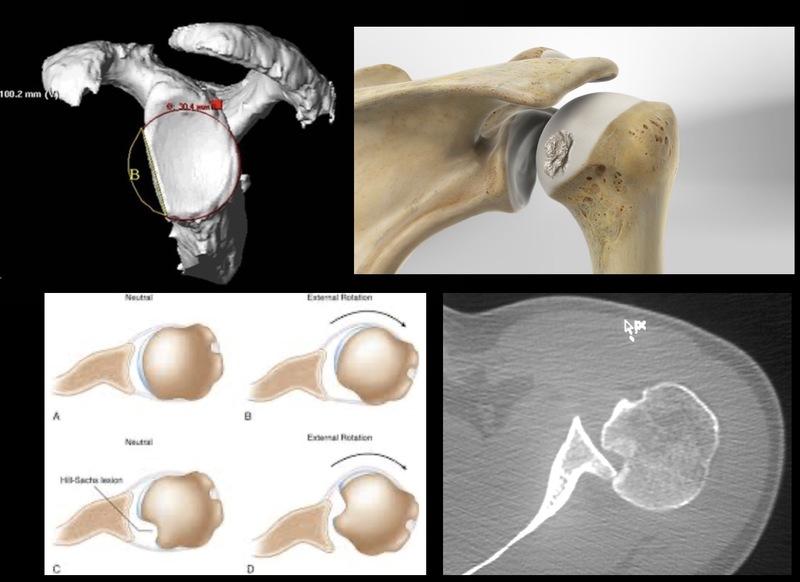

肩の構造=ゴルフ tee

肩を脱臼すると、土台が欠けたり、ボールが傷つきます

欠けると肩が不安定になります